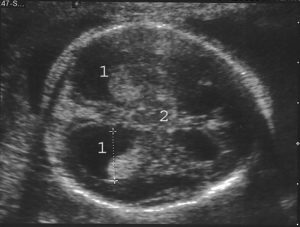

Сканированием измеряют головку будущего ребенка, и основным параметром при этом является ширина желудочков, расположенных сбоку, их размер не должен превышать 10 мм.

УЗИ проводят на 17 неделе и делают повторное исследование на 22 неделе, но средним сроком является 26 неделя беременности. Гидроцефалия на УЗИ плода говорит о наличии сопутствующей инфекции, с которой необходимо начинать бороться немедленно.

Основной метод диагностики – УЗИ. По средствам сканирования измеряют объем и размеры головки малыша, оценивают величину боковых желудочков.

Норма ширины этого показателя составляет 10 мм, превышение этих показателей считается патологическим.

Последствия патологии

Все те факторы, которые грозят возникновению негативных последствий, зависят от дефектов развития и причин нарушения. К примеру, если размер боковых желудочков не достиг 15 мм, и при этом никаких иных патологий не выявлено, то это легко поддается лечению во время прохождения беременности. Тогда малыш родится здоровым.

Если же размеры желудочков превышают 15 мм, то интенсивно начинает развиваться гидроцефалия плода, которая неблагоприятно отразится на будущем ребенке. Последствием при наличии водянки может быть и летальный исход, а также возможны заболевания центральной нервной системы.